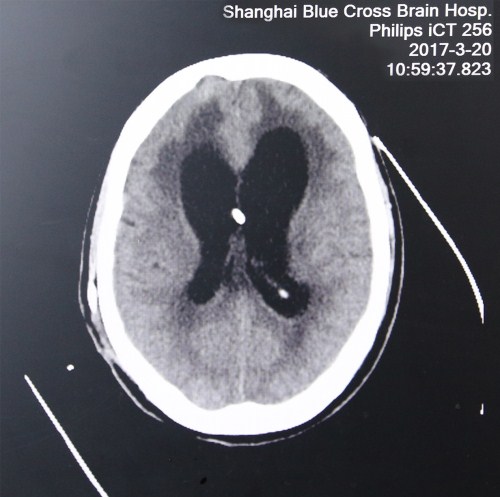

入院初头颅CT影像:之前做过分流手术,置入两分流管,脑室扩大、肿胀、有软化、渗出,脑压高

入院诊断:1.重度颅脑损伤 2.重度脑积水 3.外伤性癫痫 4.严重肺部感染。

入院情况:神志不清,气管切开,深昏迷状态;反复高热,查体不能合作,头颅部见手术疤痕,背部及骶尾部可见陈旧性压疮,左上肢屈曲内收,屈肌张力增高,右侧肢体肌力0级。